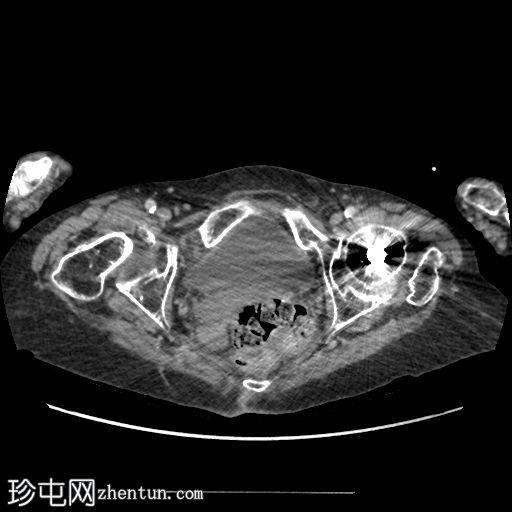

轴位增强扫描(门静脉期)

三个月后,患者因急性腹痛伴呕吐就诊。

影像表现为小肠梗阻,移行区位于右侧闭孔疝处。疝囊内有少量积液,提示缺血性改变。

无气腹。